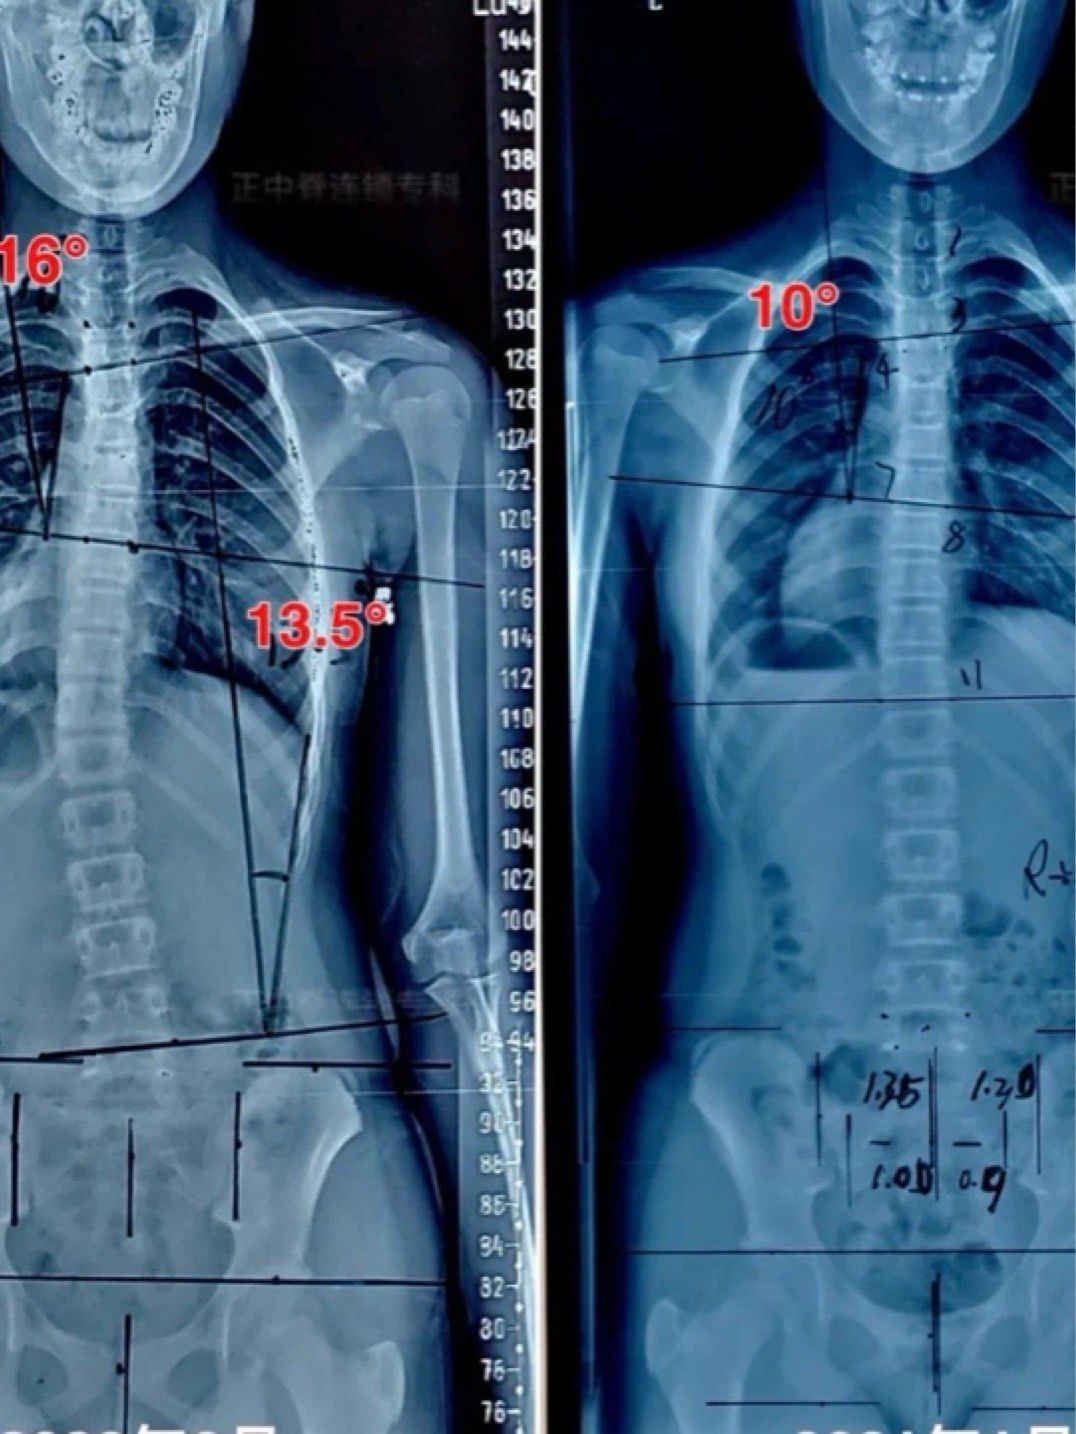

16岁女孩脊柱侧弯胸弯38度腰弯30度